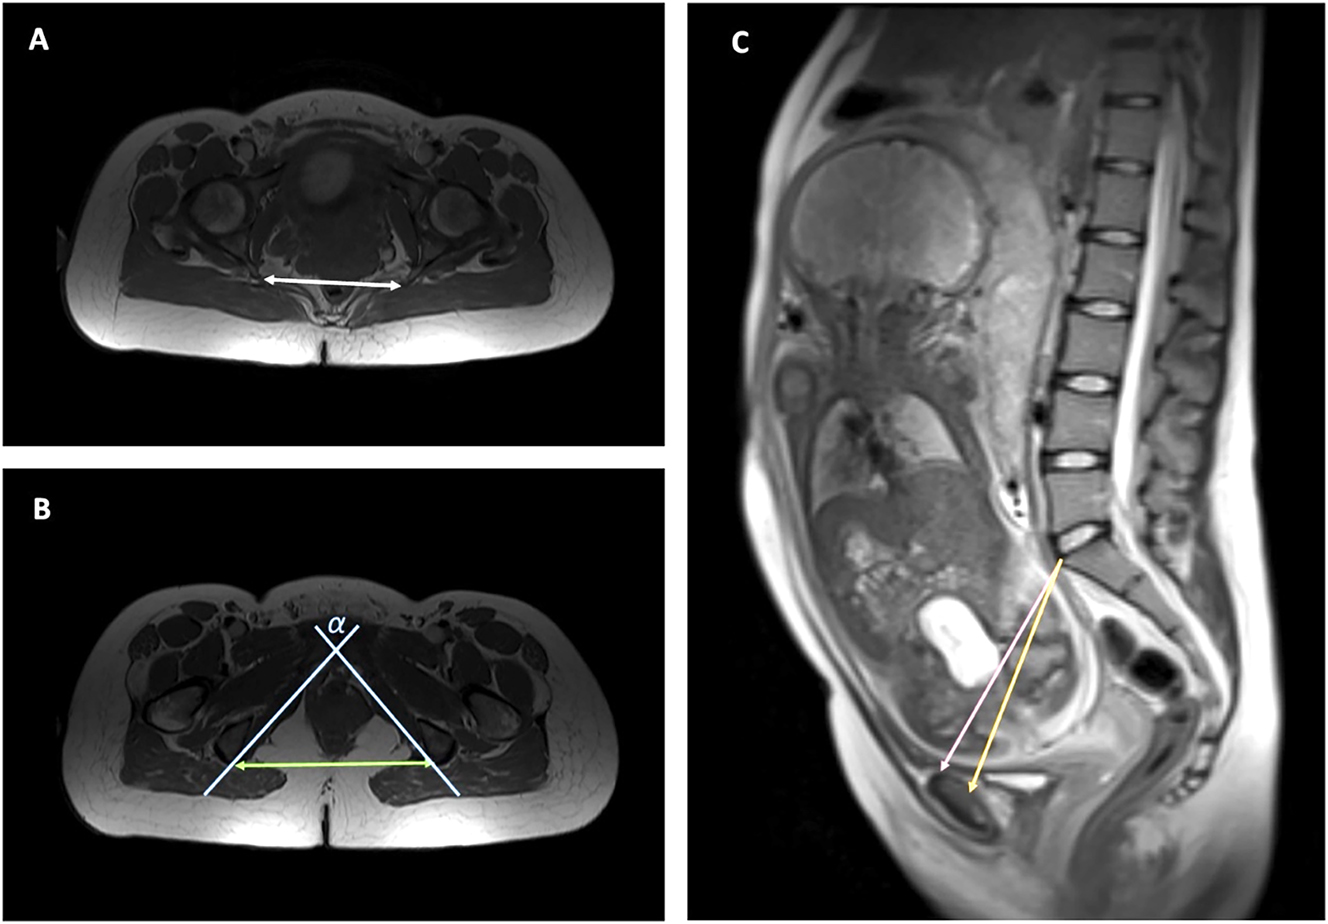

Intertubal distance, pubic angle, obstetric and true conjugate, and fetal biparietal and occipitofrontal diameters were measured by an experienced radiologist (8 years experience in urogenital imaging) (see Figures 2 and 3). The type of breech, e.g. complete, incomplete or Frank breech, was described as well as placental position and possible maternal pathologies. In addition, all studies were reviewed by a consultant paediatric radiologist.

Axial and sagittal measurements of the maternal pelvis. (A) Axial view of the maternal pelvis, measurement of interspinous distance (white double arrow), (B) axial view of the maternal pelvis, measurement of intertuberous distance (green double arrow) and pubic angle (α) (blue lines), (C) measurement of obstetrical (pink) and true conjugate (orange).